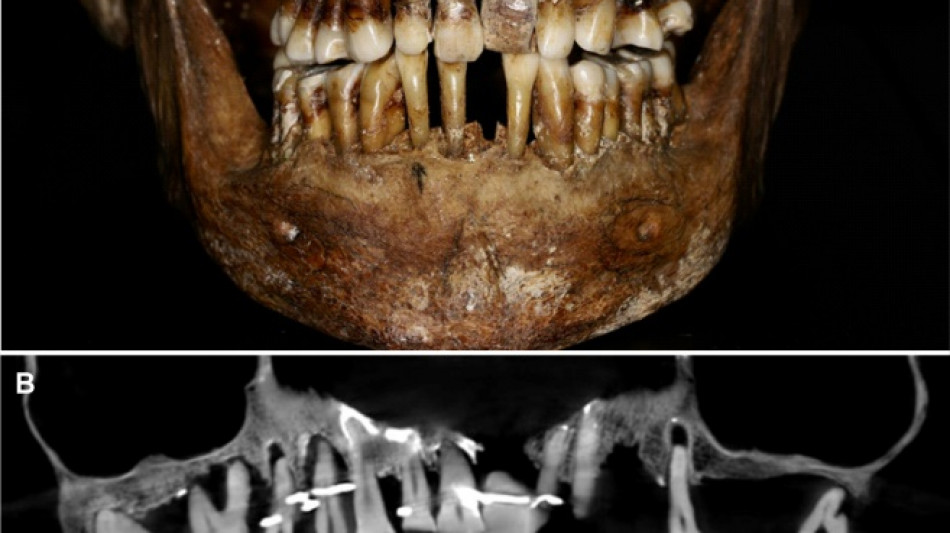

French aristocrat's golden dental secret revealed 400 years on

Scientists have discovered the long-buried secret of a 17th-century French aristocrat 400 years after her death: she was using gold wire to keep her teeth from falling out.

Embalmed in a lead coffin, her skeleton -- and teeth -- were remarkably well preserved.

At the time the archaeologists noticed that she had a dental prosthetic, but they did not have advanced scanning tools to find out more.

A "Cone Beam" scan, which uses X-rays to build three-dimensional images, showed that gold wire had been used to hold together and tighten several of her teeth.

She also had an artificial tooth made of ivory from an elephant -- not hippopotamus, which was popular at the time.